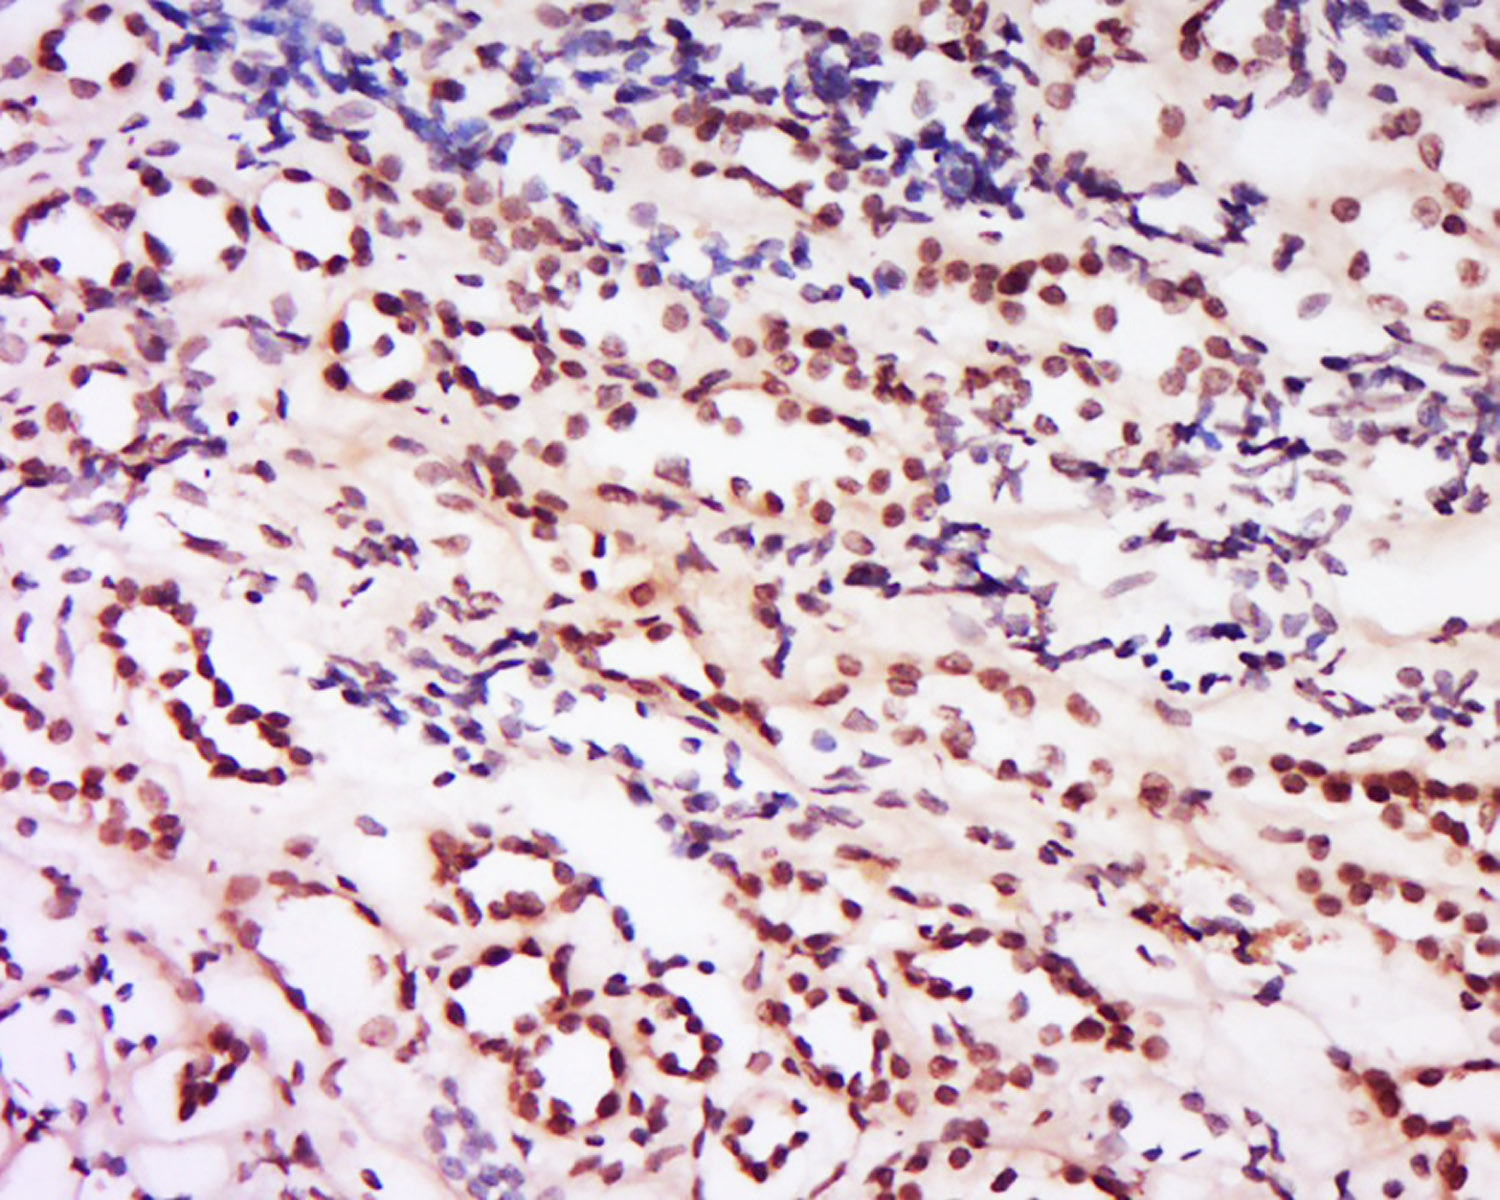

Tissue/cell: human kidney tissue; 4% Paraformaldehyde-fixed and paraffin-embedded;

Antigen retrieval: citrate buffer ( 0.01M, pH 6.0 ), Boiling bathing for 15min; Block endogenous peroxidase by 3% Hydrogen peroxide for 30min; Blocking buffer (normal goat serum,C-0005) at 37℃ for 20 min;

Incubation: Anti- Phospho-Mst2 Polyclonal Antibody, Unconjugated(bs-4634R) 1:200, overnight at 4°C, followed by conjugation to the secondary antibody(SP-0023) and DAB(C-0010) staining